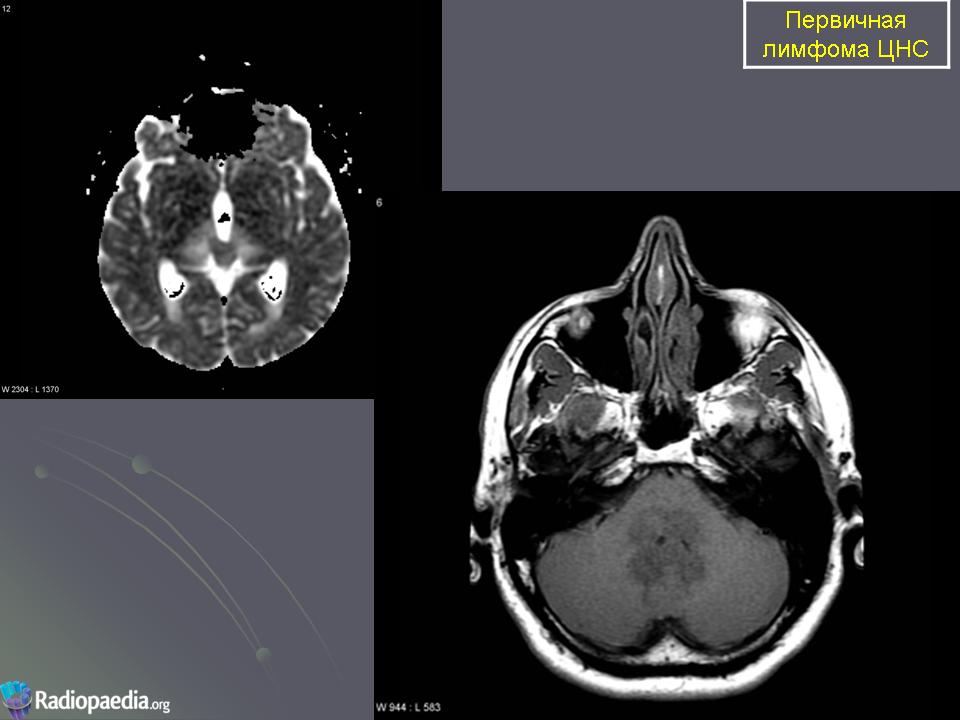

Первичные лимфомы ЦНС. Вс, 22/05/2011 - 21:45 #1 Катенёв Валенти... Не на сайте Был на сайте: 7 лет 5 месяцев назад Зарегистрирован: 22.03.2008 - 22:15 Публикации: 54876 Продолжение.Приложения:

Продолжение.